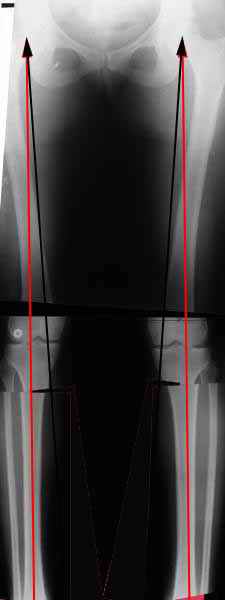

Вот, с учетом и без учета, и на разных уровнях...

Саша Артемьев, может, для данного случая свой вариант нарисуешь?